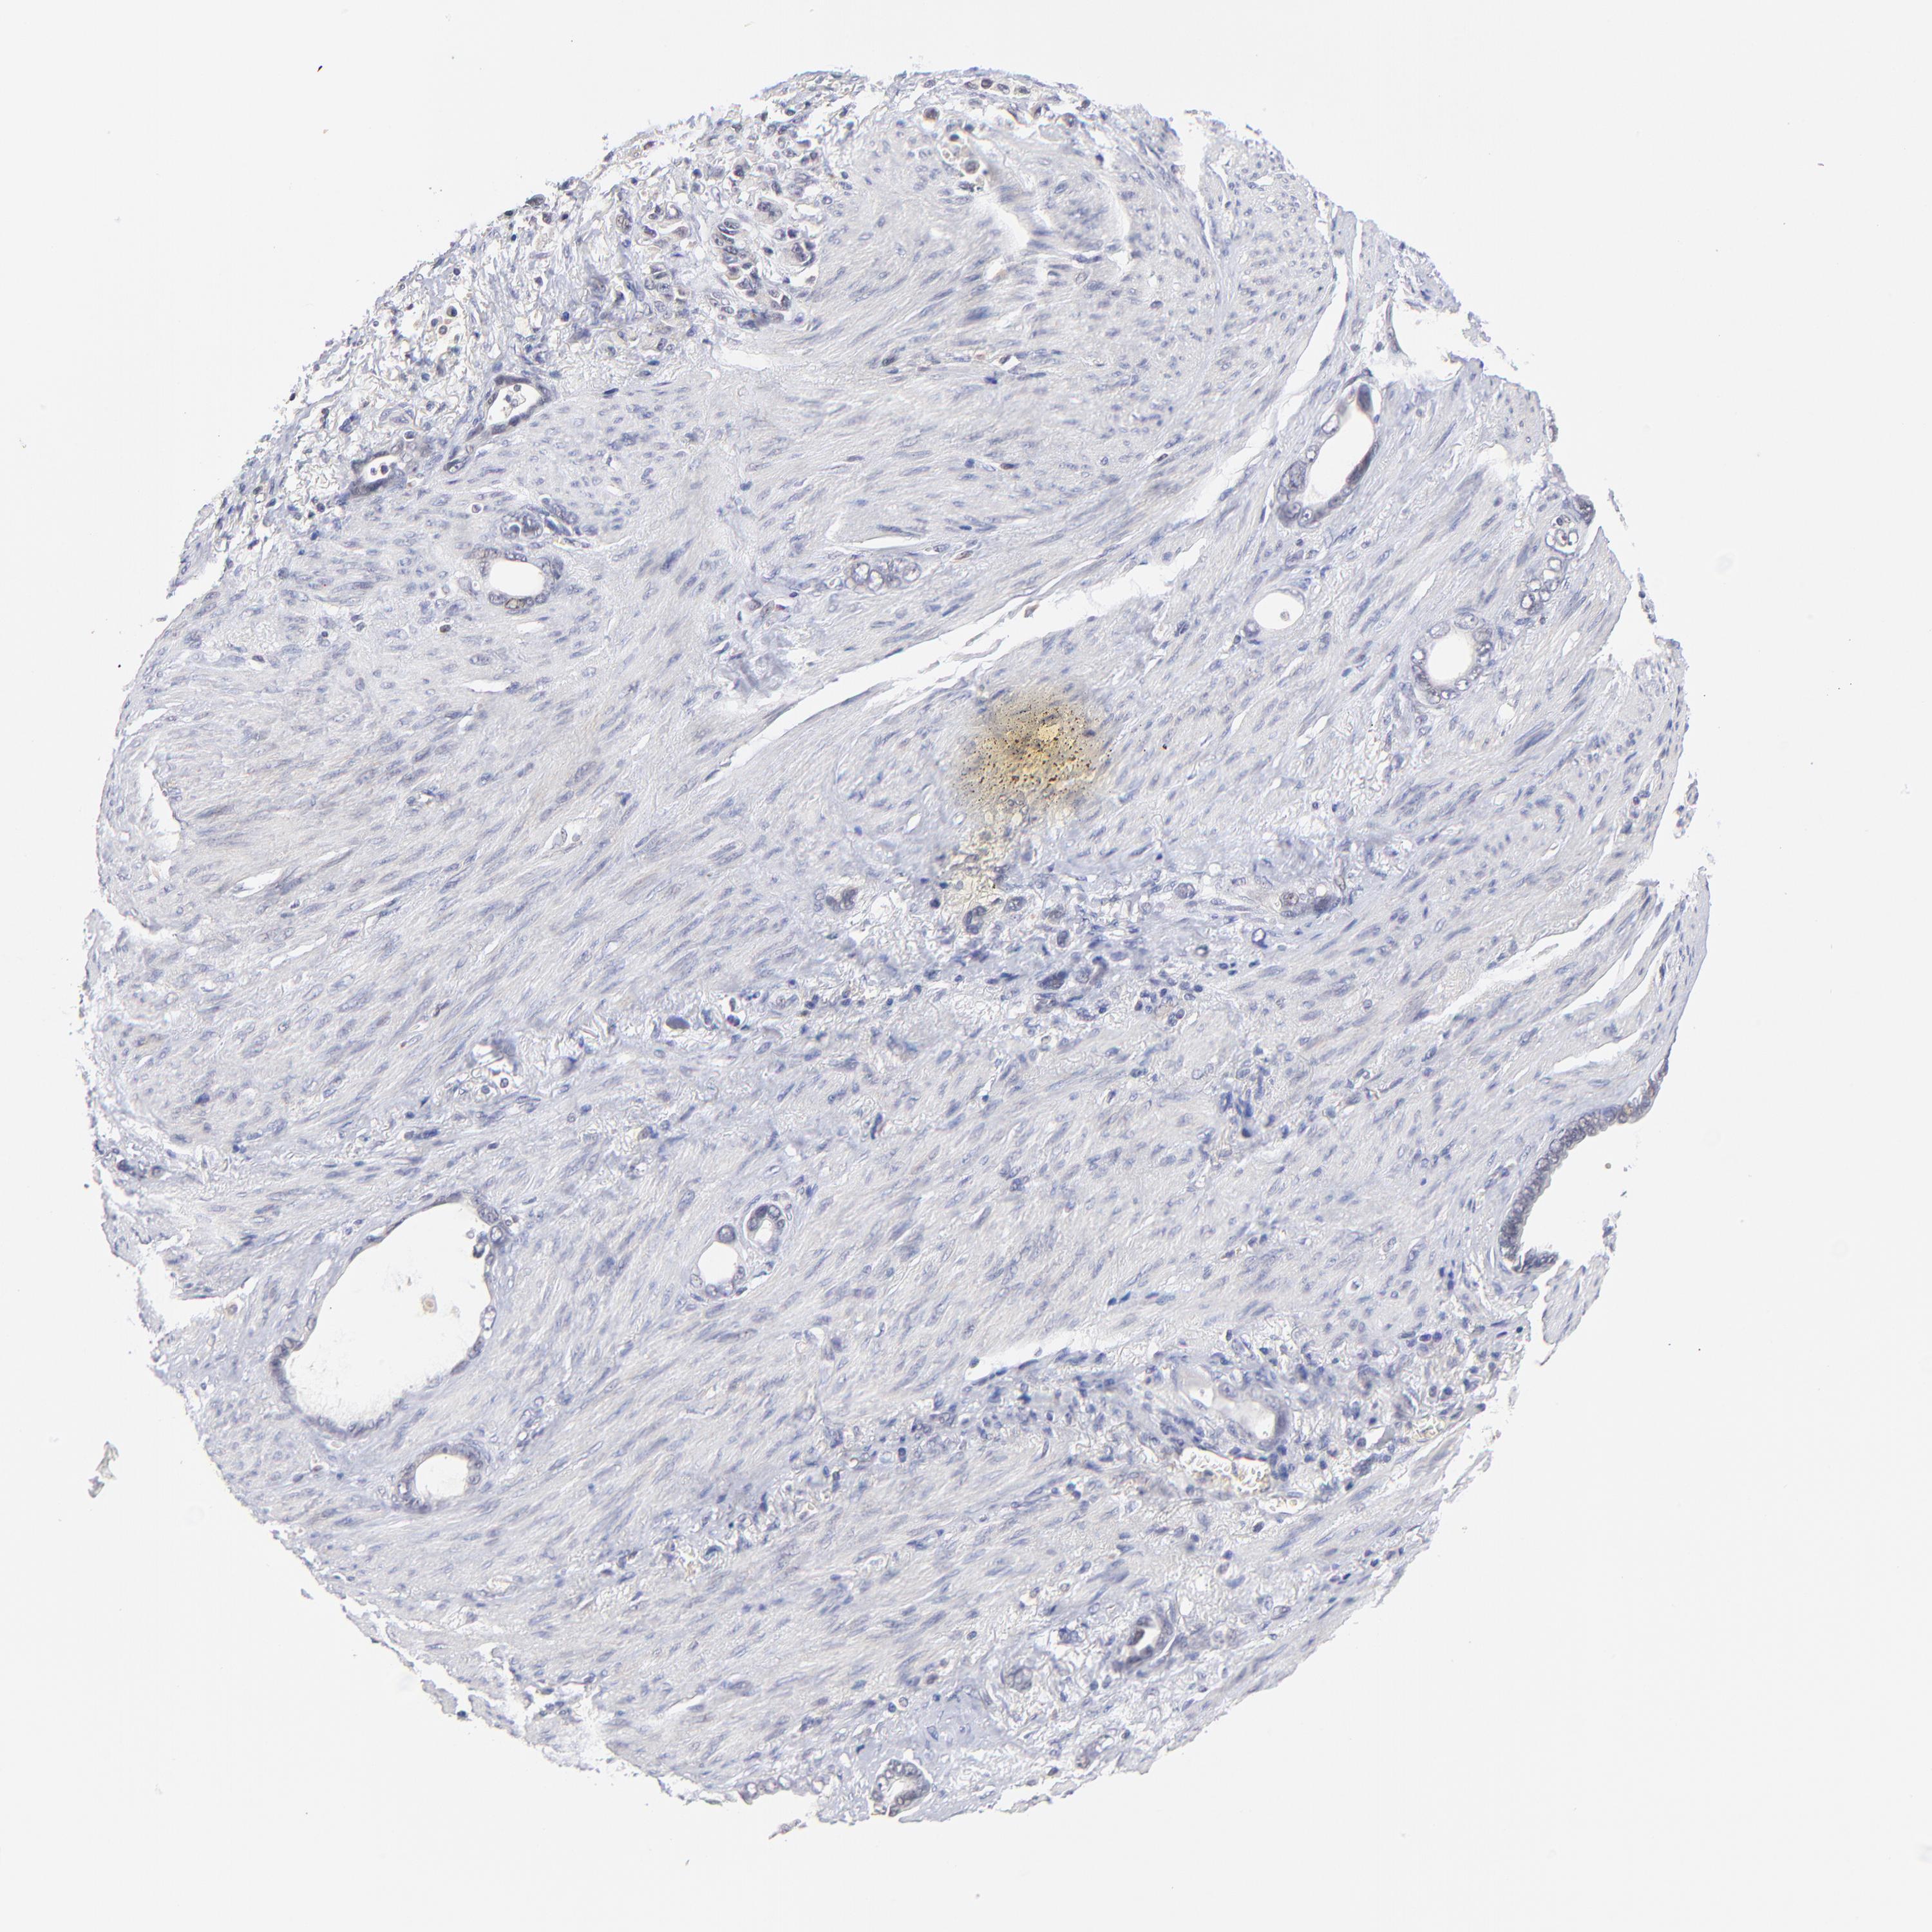

STOMACH CANCER - Protein expressioni

A mouse-over function shows sample information and annotation data. Click on an image to view it in a full screen mode. Samples can be filtered based on level of antibody staining by selecting one or several of the following categories: high, medium, low and not detected. The assay and annotation is described here.

Note that samples used for immunohistochemistry by the Human Protein Atlas do not correspond to samples in the TCGA dataset.

Antibody stainingi

Antibody staining in the annotated cell types in the current human tissue is reported as not detected, low, medium, or high, based on conventional immunohistochemistry profiling in selected tissues. This score is based on the combination of the staining intensity and fraction of stained cells.

Each image is clickable and will lead to virtual microscopy that enables deeper exploration of all samples and also displays staining intensity scores, fraction scores and subcellular localization as well as patient and tissue information for each sample.

Antibody HPA003141

Staining

High

Medium

Low

Not detected

Intensity

Strong

Moderate

Weak

Negative

Quantity

>75%

75%-25%

<25%

None

Location

Nuclear

Cytoplasmic/membranous

Cytoplasmic/membranous,nuclear

Adenocarcinoma, NOS